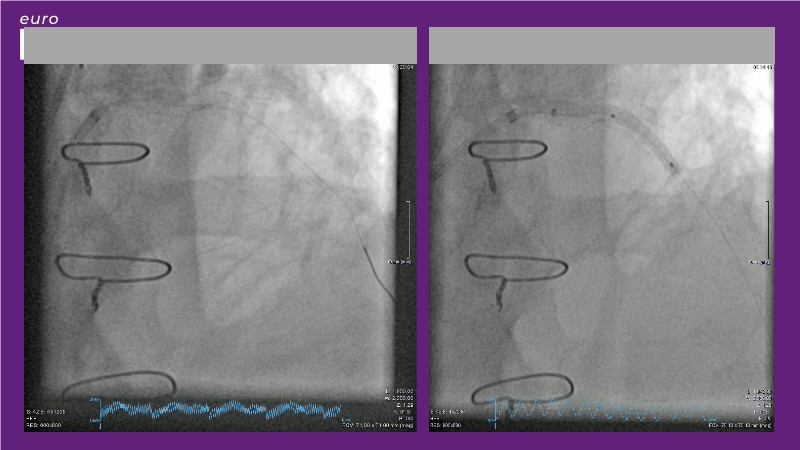

Explore how real-world data and evolving evidence are reshaping IV antithrombotic strategies in complex PCI. This EuroPCR 2025 session brings together urgent clinical cases—including STEMI patients in shock—and highlights key insights from the SMILE registry. Learn how transition protocols from cangrelor to oral P2Y12 inhibitors are applied in practice, compare approaches across Europe and the US, and get a forward-looking perspective on what’s next for IV therapies in 2025. A must-watch for anyone managing high-risk PCI.